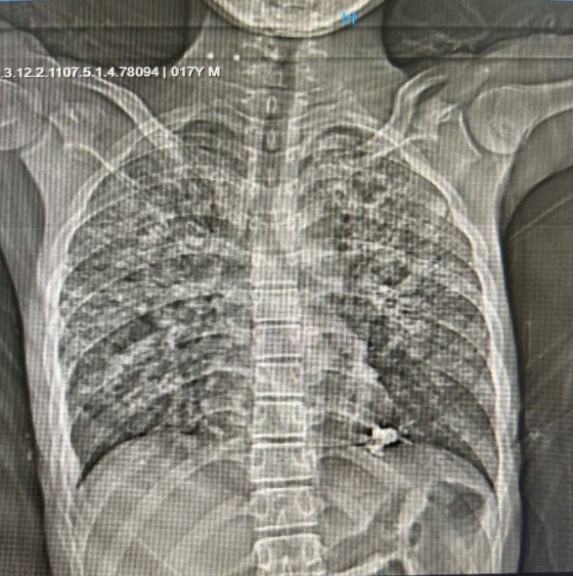

BỆNH LAO PHỔI

Lao phổi là một bệnh hô hấp dễ lây lan trong cộng đồng. Những biểu hiện điển hình như: Ho kéo dài hơn 3 tuần (ho khan, ho có đờm, ho ra máu); Đau ngực; Sốt nhẹ, gai rét về chiều, đổ mồ hôi trộm về đêm; Chán ăn, mệt mỏi, gầy sút cân.